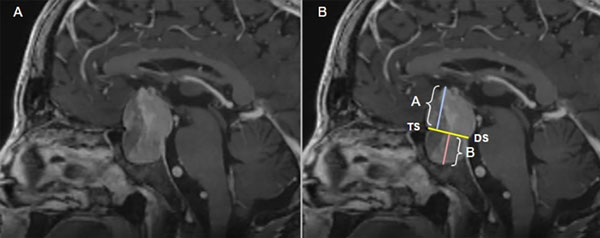

Se estableció un parámetro radiológico para valorar la extensión supraselar e infraselar, trazando una línea en el plano sagital desde el tuberculum selar al dorso selar (plano TS-DS), replicando la extensión del diafragma selar. A partir de este plano imaginario se traza una línea con una angulación de 90° tomando como punto de referencia el cenit tumoral. De esta forma, se cuantifica el máximo grado de extensión cefálica tumoral. Asimismo, se ideó una clasificación para subdividir en grupos según la distancia de extensión tumoral cefálica, estos son los grupos A (extensión 1-5 mm en sentido cefálico desde el plano TS-DS), el B (extensión de 6-10 mm), el C (extensión de 11-15 mm), y el subgrupo D (para aquellas lesiones que presentan una extensión superior a los 15 mm). A partir del plano TS-DS, además, se planteó trazar un plano con la misma angulación en sentido caudal al “nadir” tumoral, y así se cuantifica el máximo grado de extensión caudal. De estas medidas se obtiene el “coeficiente selar" (valor obtenido de la relación entre la extensión tumoral supra y subyacente al plano “tuberculum selar - dorso selar“ TS-DS) (Figura 4). Gracias a estos valores se logró obtener una medición cuantitativa y objetiva de la extensión tumoral en un plano cefalocaudal de forma simultánea, y así poder establecer un valor que determina si una lesión presenta mayor extensión supra o infraselar, con el fin de determinar el compromiso del diafragma selar y estimar el riesgo de desarrollo de fístula de LCR.

Figura 4. Resonancia magnética de encéfalo ponderada en una secuencia T1 con contraste (gadolinio) en un plano sagital. A) Imagen tumoral selar. B) Se han graficado, para la interpretación: el plano tuberculum selar – dorsal selar (TS-DS) y las variables de extensión tumoral suprayacente al plano TS-DS (A = 29.07 mm) y la extensión tumoral subyacente al plano TS-DS (B= 13.34 mm). Con la medición de estas variables se obtiene el “coeficiente selar” (CS= A/B).

Además, la variable imágenes del “coeficiente selar” (relación entre la extensión tumoral suprasubyacente al plano TS-DS) (ver Figura 4) resultó tener un valor estadísticamente significativo (p <0.001) al momento de establecer una tendencia predictiva en relación al desarrollo de FiOP. Con este valor se puede dilucidar que aquellas lesiones que tengan una extensión tumoral suprayacente al plano TS-DS mayor en relación a la extensión subyacente, tendrán un valor ≥ a 1, lo que logra establecer una relación directamente proporcional: cuanto mayor sea el valor del coeficiente selar, mayor daño de estructuras suprayacentes al límite superior del compartimento y, por consiguiente, del diafragma selar.